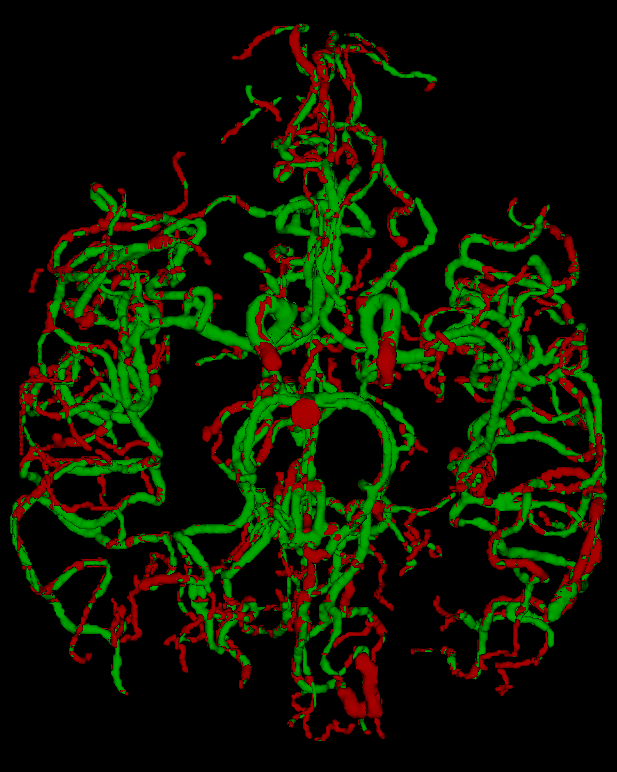

We perform three experiments to evaluate our method. (1) We compare the performance of our approach with commonly used unsupervised methods for vessel segmentation: Frangi [7], Sato [20], Hybrid Hessian [14] and Meijering [13] filters on four 2D datasets and two 3D datasets, all of which are publicly available. (2) We study the efficiency of learned representation for the downstream vessel segmentation task. To do that, we compare our method with existing self-supervised methods. (3) We examine the efficacy of the bifurcation loss in segmenting the regions around bifurcation points in 2D compared to methods which do not consider bifurcations.

Datasets: For the 2D experiments, we use four publicly available retinal image datasets: DRIVE [16], STARE [10], HRF [1] and RITE [11]. The DRIVE and RITE datasets consist of 40 images, divided into a training and testing set of 20 images. The STARE database consists of 20 images, each image with two sets of segmented images. The HRF dataset consists of 45 retinopathy images which we divide into a training set of 21 images and testing set of 24 images. For 3D vessel segmentation, we use the VESSEL12 dataset [19] consisting of 20 CT lung images from a variety of sources. The dataset also contains 3 images with sparsely annotated vessel and non-vessel locations along 3 axial slices, which we use as a test set. We also use the TubeTK dataset [2] which consists of 3D MRA images of 100 healthy patients of size . We use 42 images with ground truths as the test set, and the remaining images are used for training the network.

We compare our model against popular vessel enhancement methods, including Frangi, Sato, Hessian, and Meijering filters. All the methods take raw images as input and produce a vessel-enhanced image as output. The enhanced image is segmented into a binary map using a hard threshold, which is selected to achieve a maximum dice score over the training dataset. The performance is then reported over the test set using the hard threshold. Table 1 presents a quantitative comparison of different vessel-segmentation methods as a binary classification problem. We reported results on five measures, namely, the area under the curve (AUC) of ROC curves, accuracy (acc), local-accuracy (LAcc) [15], and dice score.

For the VESSEL12 dataset, we drop the Dice score since we do not have access to a dense ground truth. Therefore, we treat the problem as a classification problem and compare sensitivity (sens) and specificity (spec) as well. For TubeTK, we compare the Dice score of the methods with the dense ground truth. The results are summarized in Table 2. Similar to 2D, our method performs consistently across datasets, and has a significantly higher Dice score. Without using any annotations for training, our method outperforms other commonly used unsupervised vessel enhancement methods. Since vessel segmentation is a sparse segmentation problem, the critical metrics are Dice score and Local Accuracy, on which our method has a significant improvement over baselines.

| VESSEL12 | TubeTK | ||||||

|---|---|---|---|---|---|---|---|

| Method | Acc | Spec | Sens | AUC | Acc | AUC | Dice |

| Sato | 79.1 | 0.81 | 0.74 | 0.88 | 91.17 | 0.74 | 0.15 |

| Meijering | 90.16 | 0.89 | 0.92 | 0.96 | 97.25 | 0.83 | 0.34 |

| Frangi | 96.88 | 0.97 | 0.96 | 0.97 | 98.79 | 0.90 | 0.42 |

| Ours | 95.49 | 0.92 | 0.99 | 0.99 | 99.05 | 0.95 | 0.59 |